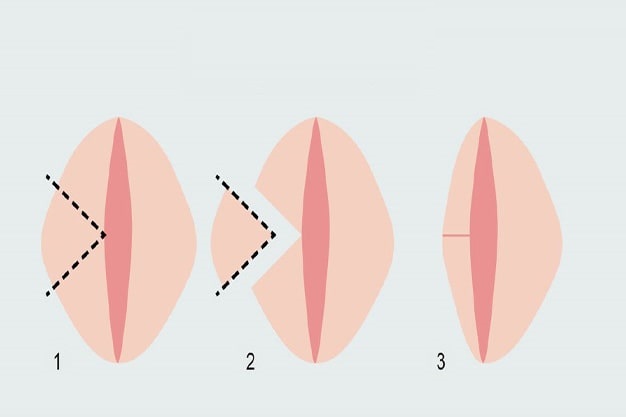

بهترین دکتر لابیاپلاستی در تبریز + لیست 10 تایی